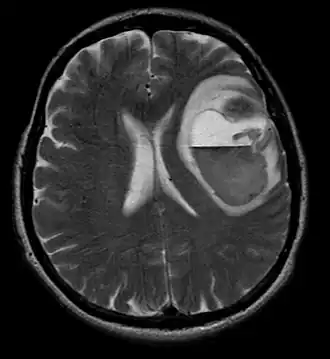

Computertomografie (CT) en magnetische resonantiebeeldvorming (MRI) kunnen neoplasie in de hersenen effectief detecteren. MRI is gevoeliger dan CT voor het identificeren van laesies, maar heeft contra-indicaties voor patiënten met pacemakers, incompatibele prothesen, metalen clips en andere. CT blijft de voorkeursmethode om calcificaties in laesies of boterosie van het kalotje of de basis te detecteren. Het gebruik van contrastmiddelen, die gejodeerd zijn in het geval van CT en paramagnetisch (gadolinium) in het geval van MRI, maakt het verkrijgen van informatie over de vascularisatie en integriteit van de bloed-hersenbarrière mogelijk, een betere definitie van de tumorachtige tumor vergeleken tot het omringende oedeem en het genereren van hypothesen over de mate van maligniteit. Het radiologisch onderzoek maakt ook een beoordeling mogelijk van de mechanische effecten en de daaruit voortvloeiende veranderingen in hersenstructuren als gevolg van de tumor, zoals hydrocefalus en hernia's, waarvan de effecten fataal kunnen zijn. Ten slotte kan deze diagnostiek, ter voorbereiding op een operatie, worden gebruikt om de locatie van de laesie of de infiltratie van de tumor in vitale delen van de hersenen te bepalen. Voor dit doel is MRI efficiënter dan CT omdat het driedimensionale beelden kan opleveren. Diagnostische radiologische beeldvormingshulpmiddelen benadrukken de verandering in neoplastisch weefsel in vergelijking met normaal hersenparenchym (door veranderingen in elektronisch afgebeelde weefseldichtheid op CT en signaalintensiteit op MRI). Zoals de meeste pathologische weefsels zijn tumoren ook herkenbaar aan een verhoogde ophoping van intracellulair water. In het computertomogram lijken ze hypodens, dwz met een lagere dichtheid dan het hersenparenchym, in het kernmagnetische resonantietomogram met spin-roosterrelaxatie hypointenseen in spin-spin ontspanning evenals proton weging (PD) hyperintens.

Aan -MRI toont een intracraniële tumor als een massieve laesie die na gebruik van het contrastmiddel meer luminescent kan worden. Er is echter altijd een signaalafwijking in -Magnetic resonance imaging, die de aanwezigheid van neoplasie of vasogeen oedeem aangeeft. Gewoonlijk is verhoogde luminescentie (contrastversterking) indicatief voor een tumor met een hogere graad van maligniteit. Kenmerkend voor glioblastoom is een contrastring, waarbij het lichtgevende deel overeenkomt met het vitale deel van de kwaadaardige tumor en het donkerdere -hypointens gebied dat overeenkomt met weefselnecrose.

Glioblastoom

De meest voorkomende en kwaadaardige gliaceltumoren zijn glioblastomen. Ze bestaan voornamelijk bij volwassenen uit een heterogene massa van slecht gedifferentieerde astrocytoomcellen. Ze komen meestal voor in de hersenhelften, meer zelden in de hersenstam of het ruggenmerg. Behalve in zeer zeldzame gevallen, zoals alle hersentumoren, reiken ze niet verder dan de structuren van het centrale zenuwstelsel.

Glioblastoom kan ontstaan uit een diffuus (II. graad) of een anaplastisch astrocytoom (III. graad) ontwikkelen. In het laatste geval wordt het secundair genoemd. Wanneer het echter optreedt zonder antecedenten of bewijs van eerdere maligniteit, wordt het primair genoemd. Glioblastomen worden behandeld met chirurgie, bestraling en chemotherapie. Ze zijn moeilijk te genezen en er zijn maar weinig gevallen die langer dan drie jaar overleven.